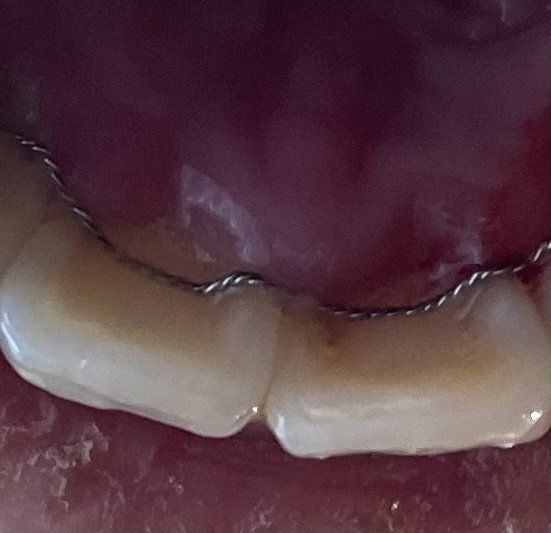

치아 앞니 뒷부분에 오른쪽 부분 고정식 유지장치가 레진이 마모된건가요? 아니면 장치가 탈락된건가요? 아니면 그냥 보이기에 그래보이는건가요? 치과 가서 유지장치를 붙여야 되는것인지 궁금합니다

사진상으로 볼때, 고정성 유지장치를 치아에 부착해주는 레진 부위가 마모된 상태로 짐작됩니다.

기존에 교정치료를 받으셨던 치과에 내원하셔서 고정성 유지장치를 교체하거나 기존의 레진을 제거한 후 다시 레진으로 부착하시면 되겠습니다.

사진이 흐리게 나와서 정확하게 말씀드리기가 애매하네요. 레진이 떨어진거라면 와이어가 움직일텐데 움직이신다면 교정하신 치과가셔서 다시 붙혀달라고 하시면될것같아요.